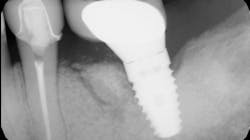

Immunomodulatory medications—used for rheumatoid arthritis, psoriasis, IBD, and lupus—represent a growing contributor to MRONJ (figures 1a and 1b).7,8